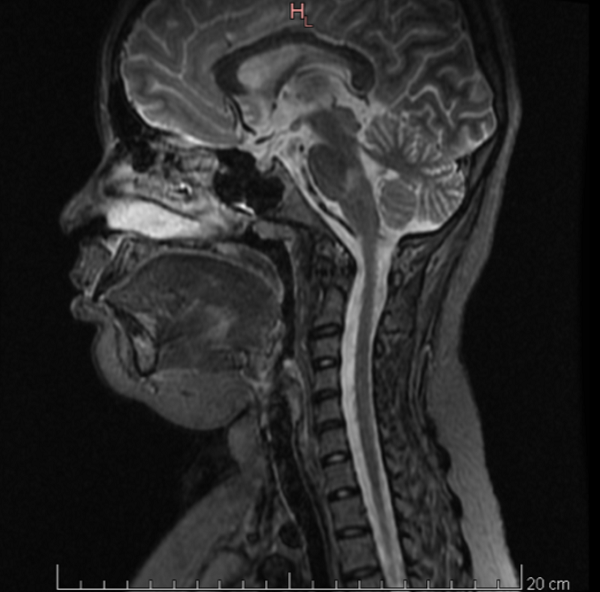

Se realiza una RM craneomedular. El estudio cerebral pone de manifiesto múltiples lesiones focales (aproximadamente 25, de entre 5 y 20 mm) predominantemente hiperintensas en secuencias T2. Afectan a la sustancia blanca yuxtasubcortical y periventricular de ambos hemisferios cerebrales, incluyendo el cuerpo calloso y el troncoencéfalo. Múltiples de las lesiones supratentoriales muestran una señal de resonancia heterogénea tanto en las secuencias T1 como T2, con un patrón interno en anillos concéntricos (patrón tipo Balo).

No se identifican lesiones en la médula espinal.